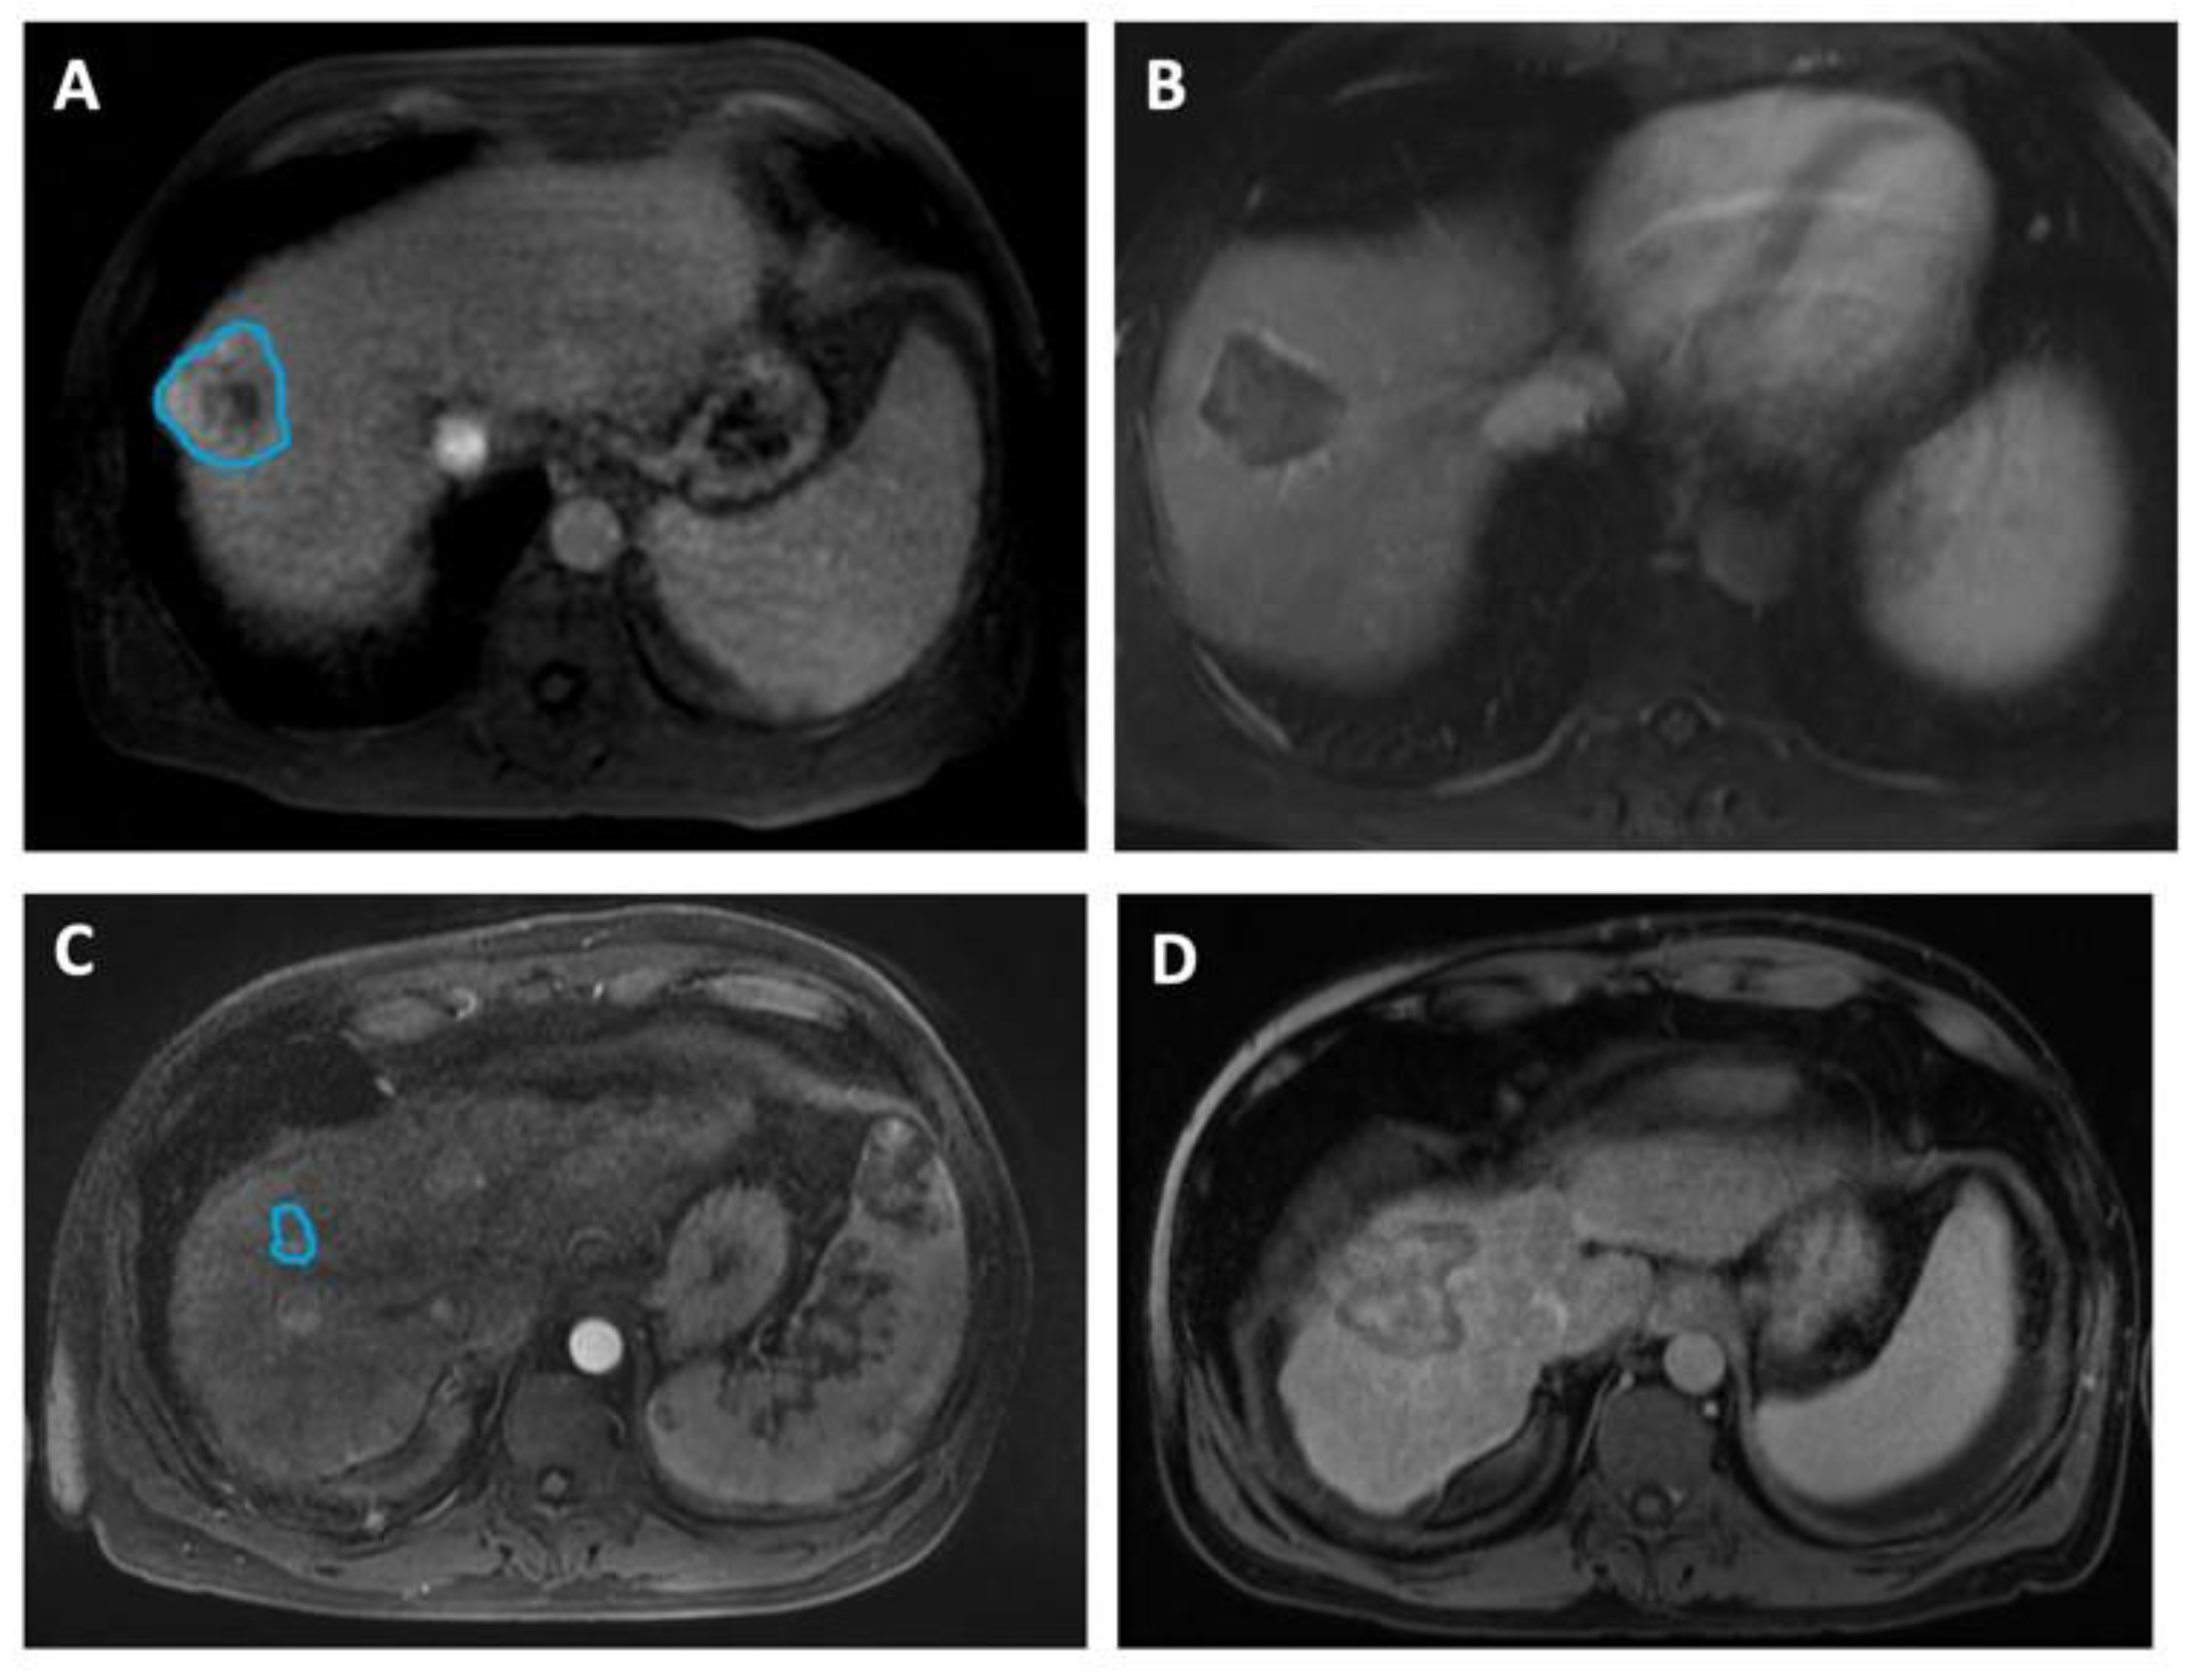

In Figure 2, we include representative MRI images illustrating visual differences in tumor heterogeneity between a Responder who underwent RFA, and a Non-responder who underwent MWA.

Figure 2. Four representative images illustrating differences in HCC tumor heterogeneity between two patients who underwent different ablation therapies and had contrasting treatment outcomes. (A,B) Axial MRI images of a 58-year-old male demonstrate (A) a 4.6 cm mass (manually delineated; blue ROI) in the right hepatic lobe, 5 days before RFA and (B) a 4.2 cm zone of ablation 50 days prior to the liver transplant. He remained recurrence-free during 1139 days of follow-up, up to the time of the transplant. The histopathologic review at the time of transplant reported complete necrosis. (C,D) Axial MRI images of a 49-year-old male illustrate (C) a 1.6 cm lesion (manually delineated; blue ROI) in the right hepatic lobe, 90 days prior to MWA and (D) a 5.1 cm ablation zone 5 days before the transplant. The patient underwent repeated procedures during the 366 days of follow-up, and exhibited incomplete pathologic response at the time of transplant.